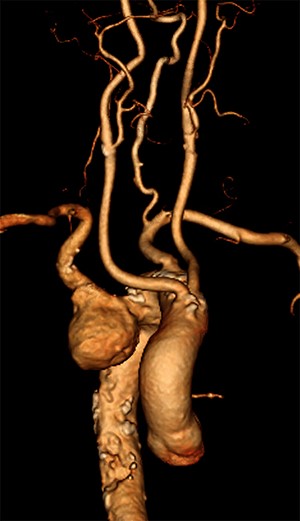

A 78-year-old male presented with sudden onset tearing chest pain with radiation to the back and associated dyspnoea and dysphagia. This was on a background of ischaemic heart disease, hypertension, hypercholesterolaemia and previous small bowel resection for neuroendocrine mesenteric malignancy. He was an ex-smoker with no personal or family history of connective tissue disorders. On computed tomography angiography (CTA) he was found to have an aberrant right subclavian artery (SCA), coursing posterior to the trachea and oesophagus, with an associated 4.4 cm Kommerell’s diverticulum (Fig. 1). Imaging also illustrated tracheal stenosis and oesophageal compression. A coronary angiogram demonstrated severe double vessel coronary artery disease. A staged procedure with aortic arch debranching and coronary artery bypass grafting (CABG), followed by a thoracic stent graft and amplatzer plug to address the Kommerrel’s Diverticulum was planned.

Computed tomography (CT) reconstruction illustrating Kommerell’s diverticulum and an aberrant right subclavian artery.